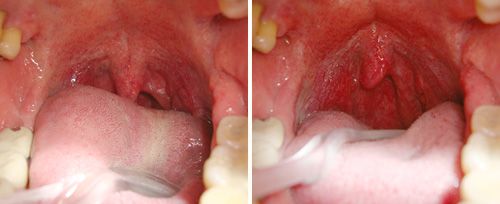

NightLase®

Snoring and Sleep Apnea Treatment

At The Dental Practice, we offer NightLase® therapy - a non-invasive, patient-friendly laser treatment designed to improve sleep quality.

A complete NightLase® treatment involves three sessions over six weeks. Results can last up to 12 months, and the procedure is easily repeatable as needed.

Unlike many other treatments, NightLase® requires no devices or chemicals – just a quick, comfortable laser procedure that helps patients breathe better and sleep more soundly.